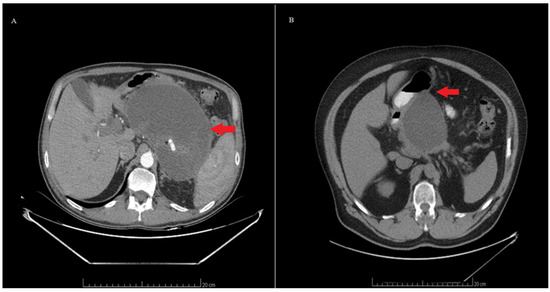

3.2. Cyst Characteristics